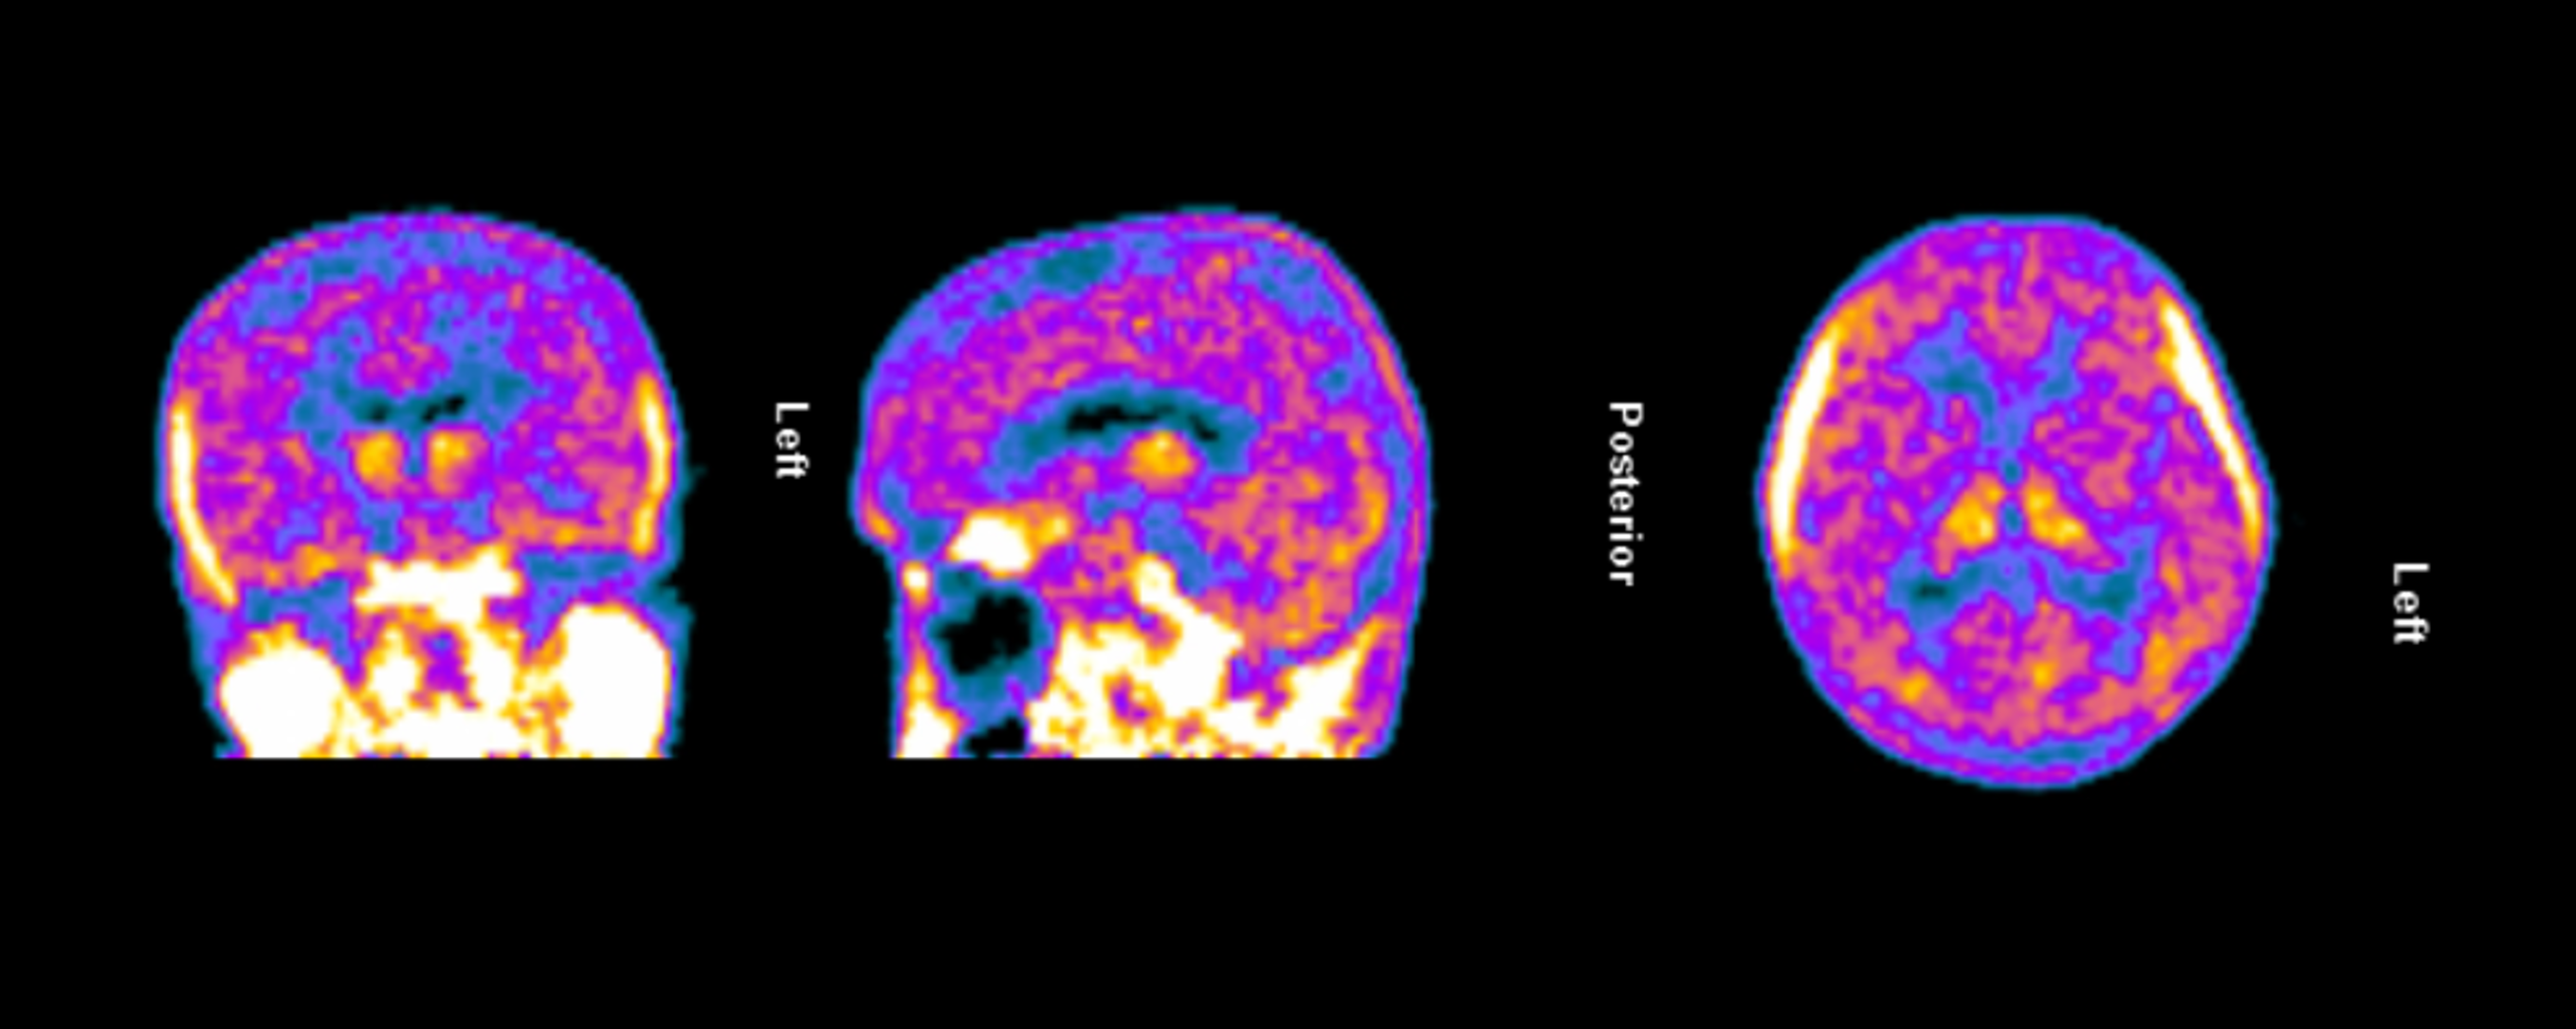

The clinical trial launch is supported by new TSPO-PET imaging evidence demonstrating persistent and widespread microglial activation in an Alzheimer’s patient despite treatment with lecanemab, confirming that neuroinflammation remains present even after amyloid plaque reduction. Lecanemab, marketed by Eisai and Biogen as Leqembi®, is one of the two FDA-approved anti-amyloid therapies for treating early Alzheimer’s and is proven to reduce beta-amyloid plaques.

Figure 1. TSPO-PET scan of an Alzheimer’s patient treated with lecanemab demonstrating persistent and widespread microglial activation throughout the brain.

Dr. Howard Weiner, Chairman of Tiziana’s Scientific Advisory Board and co-director of the Ann Romney Center for Neurologic Diseases at Brigham and Women’s Hospital, a founding member of Mass General Brigham, stated, “This PET finding is a critical insight: clearing amyloid does not turn off the brain’s inflammatory response. We believe intranasal foralumab directly addresses this residual neuroinflammation by inducing regulatory T cells to migrate to the brain and calm activated microglia — a mechanism we have already shown reduces microglial activation in secondary progressive multiple sclerosis.”